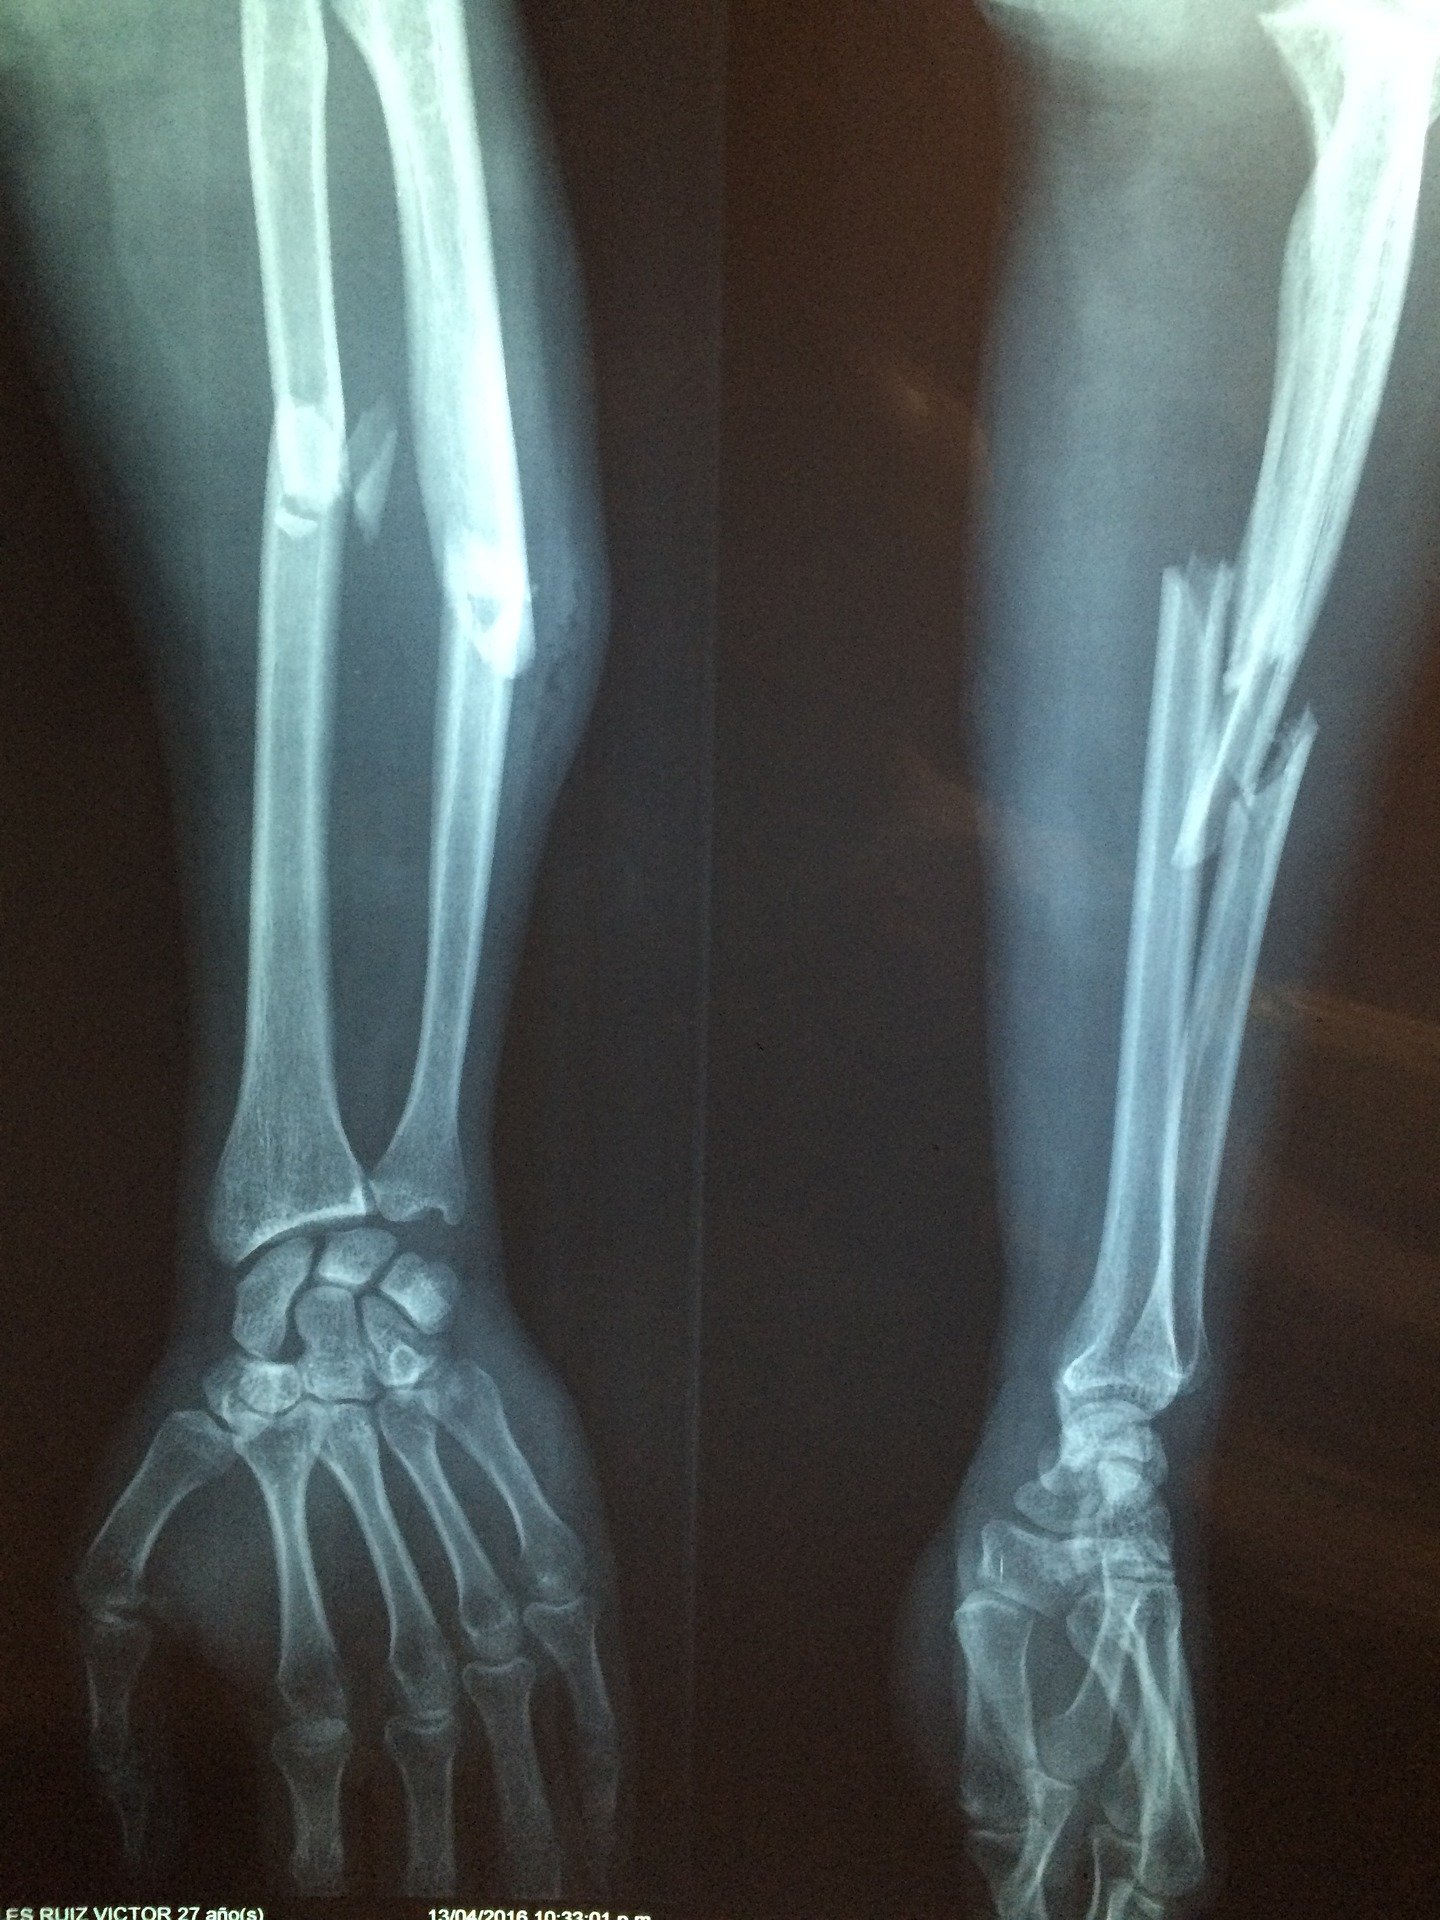

La doctora Grushenka Aguilar Esparza informó que en esta unidad de tercer nivel de atención se realizan dos mil 400 cirugías al año, de las cuales mil 700 son de cadera, con diferentes técnicas y tratamientos como osteosíntesis, -que es la colocación de una placa con tornillos-, implantes así como prótesis de última generación que permiten preservar la anatomía del paciente.